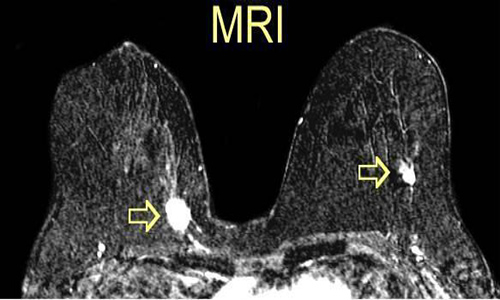

2.3 Cộng hưởng từ (MRI vú)

MRI vú có độ nhạy rất cao, thường được dùng trong các trường hợp:

- Người có nguy cơ cao (mang gen BRCA1, BRCA2).

- Kết quả siêu âm hoặc nhũ ảnh chưa rõ ràng.

- Nghi ngờ tái phát sau điều trị.

MRI không thay thế hoàn toàn siêu âm hay nhũ ảnh vì chi phí cao và có thể cho nhiều hình ảnh “giả dương tính”, nhưng lại rất hữu ích trong một số tình huống đặc biệt.